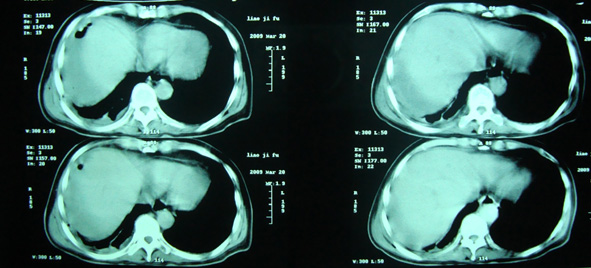

男,66岁.突发腹部疼痛,b超提示胆系水肿改变,抗生素治疗一周有好转.

后突发高热,血常规白总2万多.中性90%以上.

经治疗至17日胸闷痛摄片如9号图,20日复查如7,8号片.

结论:右侧大量胸腔积液,可疑膈下脓肿.

20日院外ct检查,片示于后.

胸部穿刺大量脓液,提示脓胸.

院外ct说排除膈下脓肿,请大家发表意见.

右侧膈肌抬高明显,胸腔内无明显积液,表现为胸膜反应,肝脏周围大量积液,并见多个液气平面。右下肺不均匀密度增高影。结合临床考虑右侧膈下脓肿并腹腔内积液、右下肺并发感染及胸膜反应,节段性肺不张不除外。

右肺下叶见大片状病灶,密度不均,其内见透光区。沿右侧胸壁见多发含气腔,其间可见间隔,其内部分可见液平。膈肌下未见异常(纵隔窗窗位太低)。应该是典型的化脓性肺炎合并脓胸。